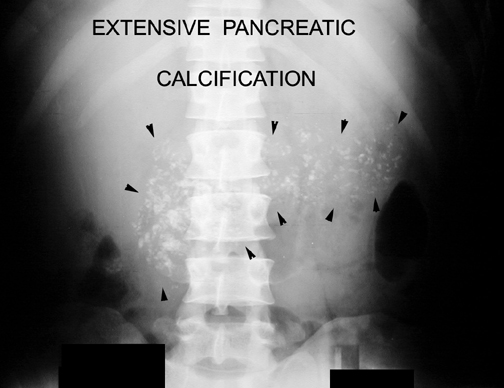

- Calcification can be seen in chronic pancreatitis.

Chronic Pancreatitis

Calcification in pancreas.

- Calcification in the pancreas